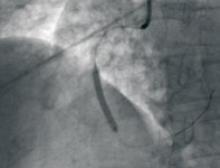

Canada is spearheading an international study to determine if an implantable cardioverter defibrillator (ICD) can prevent death from serious heart rhythm problems in those patients who’ve survived a heart attack. Heart disease is a leading cause of death in Canada and the fastest growing disease worldwide.